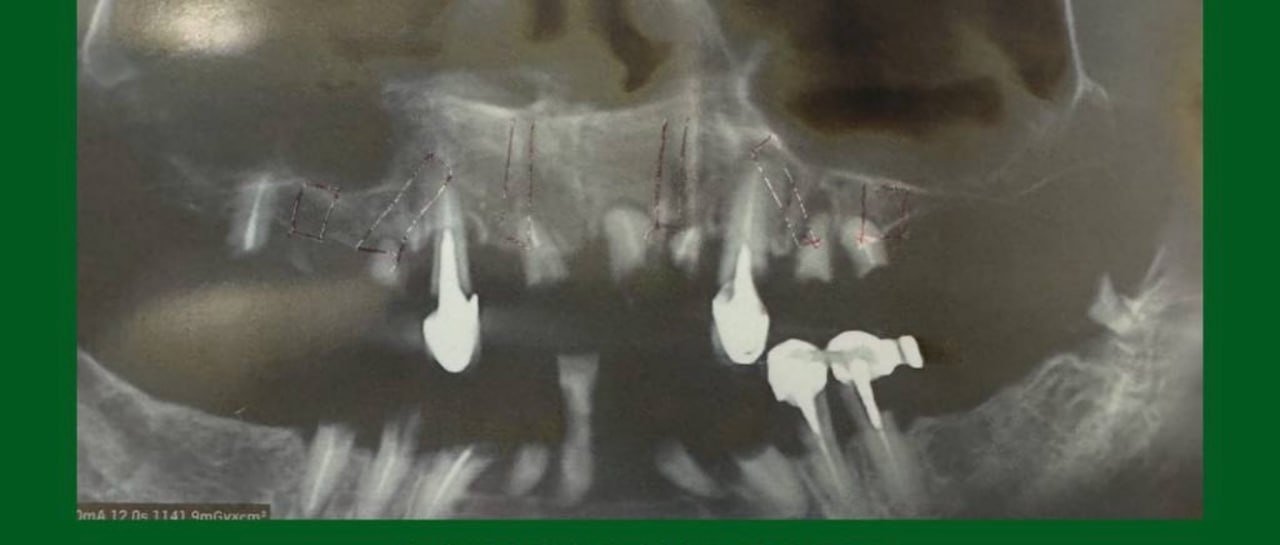

Дентальні протези – один з найефективніших і тривалих методів лікування. Імпланти – це штучно створені коренеподібні штифти з титану, які імплантуються в щелепу і служать кріпленням для зубних протезів. Цей метал максимально схожий за характеристиками на кісткову тканину і може служити до 20 років. Вимоги до коронок не менше високі, ніж до штифтів. Вони повинні бути міцними і не розколюватися при вживанні твердої їжі. Коронки робляться з металокераміки, а також діоксиду цирконію. В якості тимчасових коронок на штифт може вдягатися Металопластмаса.

- Самостійно вибрати зубний імплант — це нерозв’язне завдання для неспеціаліста. Підбір імплантаційної системи слід довірити досвідченому лікарю, який проведе 3D діагностику і запропонує відповідні варіанти реконструкції посмішки.